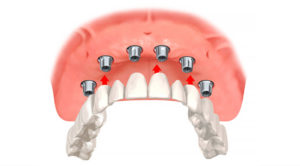

人工歯(上部構造)の装着

人工歯(上部構造)の装着のための通院回数は目安としては3~5回です。調整が必要な場合は通院回数が増えることになります。期間は1~3ヶ月です。1回法・2回法どちらの場合も、アバットメントを接続してから約1~6週間後に人工歯の型取りを行います。まず歯型をとって、お口の形に合わせた型取りの枠(トレー)を作製します。約1週間~10日後、歯型をとるのに一般的なシリコン素材を作製したトレーに入れ、口のなかにセットしシリコンが固まるのを4~5分弱待ちます。歯型をとるのにトータルで40分~1時間ほどかかります。